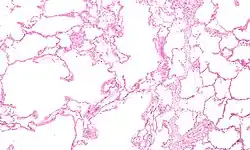

Fisiopatologia

A DPOC é um tipo de doença pulmonar obstrutiva caracterizada por uma limitação crónica e apenas parcialmente reversível das vias aéreas, verificando-se também a incapacidade de expirar por completo.[2] A limitação é o resultado da destruição do tecido pulmonar (denominada "enfisema") e de doença das pequenas vias aéreas (denominada "bronquiolite obstrutiva"). A contribuição de cada um destes fatores varia entre pessoas.[8] A destruição severa das pequenas vias respiratórias pode levar à formação de grandes bolhas de ar que substituem o tecido pulmonar. Esta forma da doença denomina-se "enfisema bolhoso".[60] Algumas pessoas com DPOC apresentam também algum grau de hiperresponsividade a irritantes semelhante ao que se verifica na asma.[18]

A DPOC tem origem numa resposta inflamatória significativa e crónica à inalação de irritantes.[8] Este estado inflamatório pode ainda ser agravado com infeções bacterianas crónicas.[58] Entre as células inflamatórias envolvidas estão os granulócitos neutrófilos e os macrófagos, dois tipos de leucócitos. Entre os fumadores estão também envolvidos os linfócitos T citotóxicos e algumas pessoas com DPOC apresentam envolvimento dos granulócitos eosinófilos de forma semelhante à asma. Parte desta resposta celular é provocada por mediadores inflamatórios, como os fatores quimiotáticos. Entre outros processos envolvidos na destruição do tecido pulmonar estão o stress oxidativo, provocado por concentrações elevadas de radicais livres no fumo do tabaco e libertados por células inflamatórias, e a destruição do tecido conjuntivo dos pulmões por proteases que não são suficientemente inibidas pelos inibidores da protease. A destruição do tecido conjuntivo dos pulmões é o que provoca o enfisema, o que por sua vez contribui para a restrição do fluxo de ar e, por último, para a má absorção e libertação de gases respiratórios. O desgaste generalizado dos músculos que muitas vezes se verifica na DPOC pode ser devido, em parte, aos mediadores inflamatórios libertados pelos pulmões no sangue.[8]

A realização de uma radiografia ao tórax e de um hemograma permitem excluir outras condições no momento do diagnóstico.[69] Os sinais característicos da DPOC observáveis em radiografia são pulmões sobre-expandidos, diafragma achatado e espaço retroesternal aumentado. Ao mesmo tempo, a radiografia permite excluir outras doenças pulmonares, como pneumonia, edema pulmonar ou pneumotórax.[70] Uma tomografia axial computorizada ao tórax permite mostrar a distribuição do enfisema pelos pulmões e pode ajudar a excluir outras doenças pulmonares.[18] No entanto, a não ser nos casos em que se planeie a realização de uma cirurgia, esta distribuição raramente influencia o tratamento.[18] Pode ainda ser realizada uma gasometria arterial para determinar a necessidade de oxigénio suplementar. Este exame é recomendado em pessoas com VEF1 inferior a 35% do previsto, com saturação periférica de oxigénio inferior a 92% e pessoas com sintomas de insuficiência cardíaca congestiva.[17] Em regiões do mundo onde é comum a deficiência de alfa-1 antitripsina, as pessoas com DPOC devem considerar a realização deste exame, sobretudo aquelas com idade inferior a 45 anos e em que o enfisema afeta a parte inferior dos pulmões.[17]

Caso grave de enfisema bolhoso

Caso grave de enfisema bolhoso -